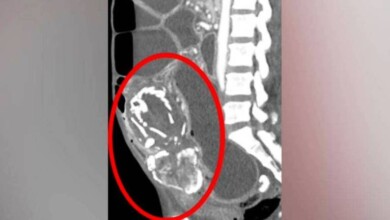

حالة نادرة.. جنين متحجر (9) سنوات يقتل أمه

في حالة نادرة سجلت (300) مرة فقط، فارقت أفريقية الحياة عن عمر ناهز الـ(50) عاماً في نيويورك، نتيجة نقص التغذية…